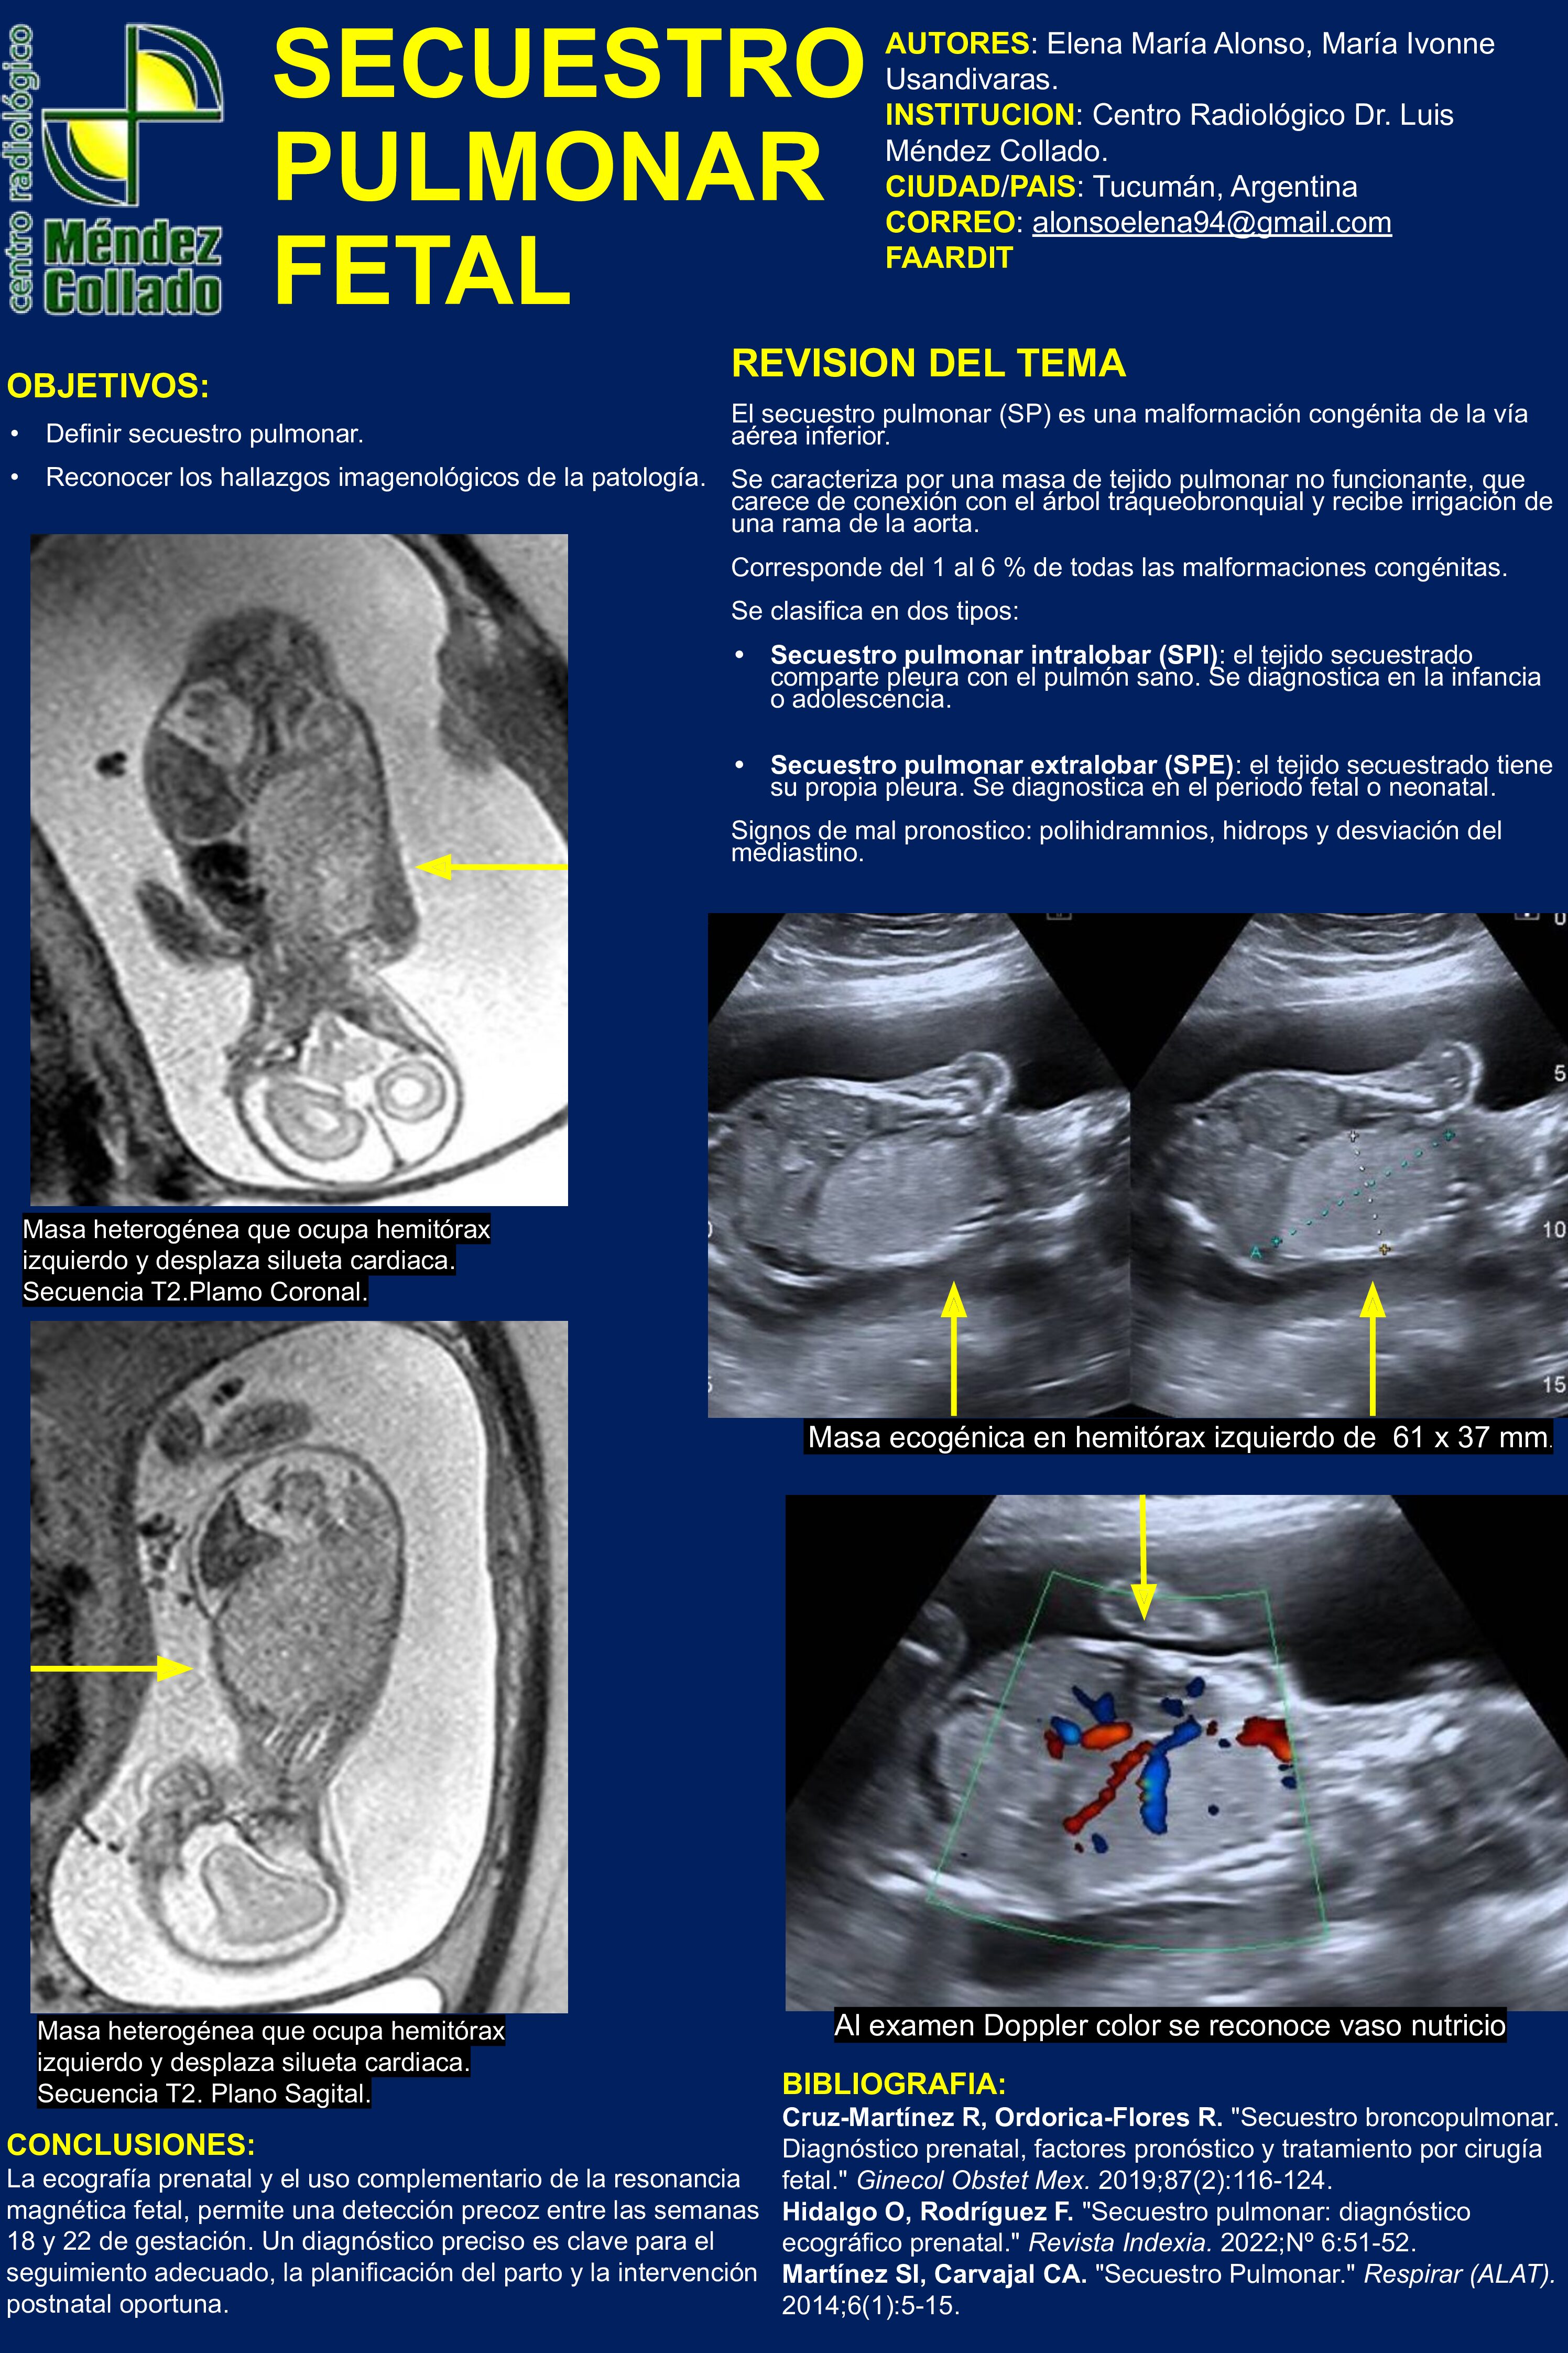

SECUESTRO PULMONAR FETAL